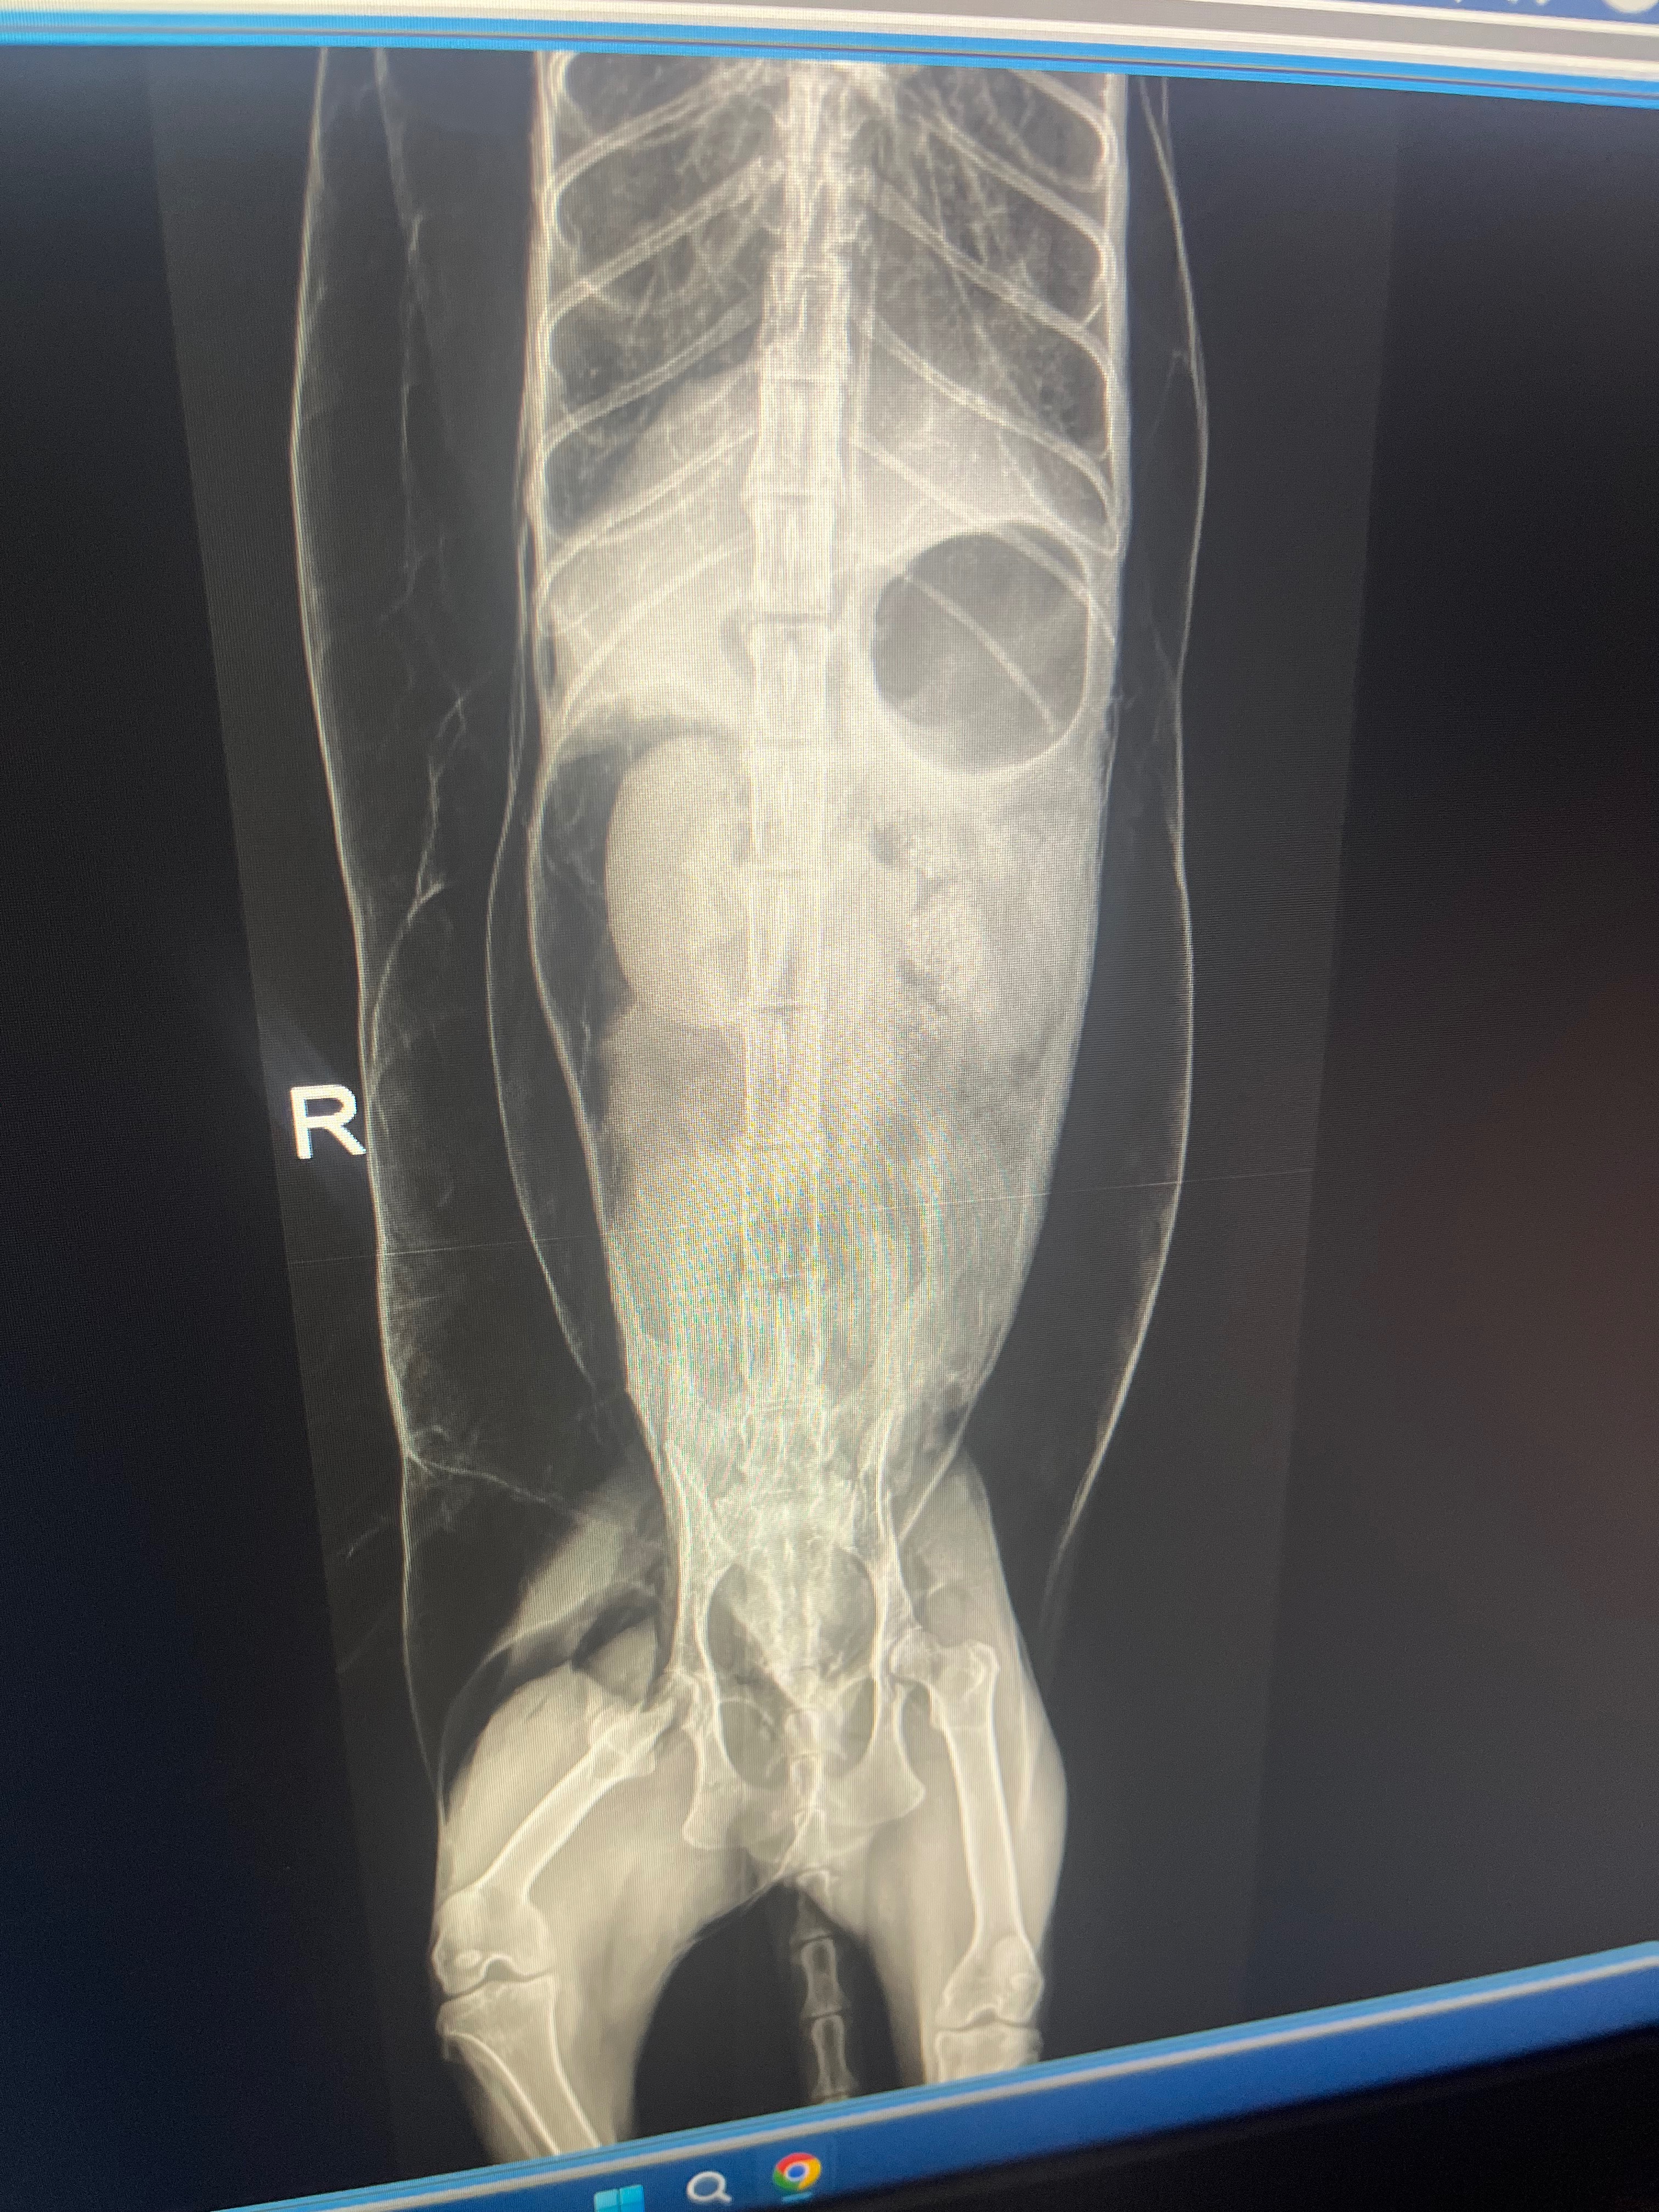

Hello anybody who reads this on 6-12-25 I had to suddenly put down waffles, she was a rescue I found outside with her sister chicken, when I got home from work she was laying in the corner not breathing right and swollen, I took her to the vet and she found pockets of gas spread throughout her entire body crushing her lungs. I had to make a sudden choice to put her to sleep, I’ve never made one of these before but I hope you can spare $5 or anything to help me out, I thank you so much to anyone who spends the time to read this and donate. I used my rent money to ease her pain and I’m in a Financial hard spot currently but I couldn’t let her suffer, thank you again